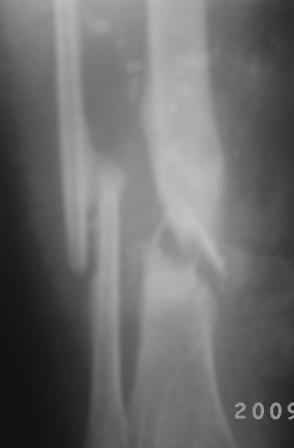

Добрый вечер, уважаемые коллеги! Обратилась женщина, 30 лет. ДТП 11 октября 2008 г. Из выписки: О/многооскольчатый перелом костей левой голени по Каплану 3В,

ПХО раны, гипсовая повязка, перевод в гор.б-цу, в 21.10.08г КДО аппаратом Илизарова(почему-то в вальгусном положении), ч-з два месяца тромбофлебит лев.н/конечности, отеки, воспаление, и аппарат сняли, с тех пор ходит в гипсовой повязке со стременем. к-рую периодически меняют, якобы кость со временем срастется.

На уровне н/з голени глубокие рубцы по передне-медиальной поверхности, умеренная отечность голени, незначительная патологическая подвижность, умерен. болезненность, ось правильная, укорочение 1,5см.

Наш план БИОС после остеоклазии м/берцовой кости. Но укорочение еще будет увеличиваться!